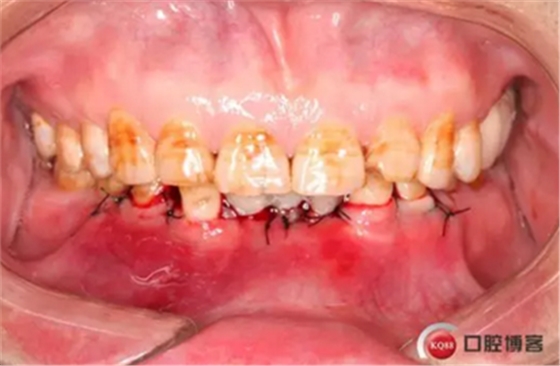

下圖是術(shù)后照片 治療過程 術(shù)前測(cè)量上下牙長(zhǎng)度比例,確定水激光冠延長(zhǎng)深度約3mm,拔除31、41,在術(shù)區(qū)減低牙槽嵴高度,32、42位點(diǎn)種植MINI型一段式種植體,使用臨時(shí)愈合帽行暫時(shí)性修復(fù)。

治療方法 針對(duì)下頜深覆頜及骨量情況,給患者提供方案:第一步通過34、33、43、44冠延長(zhǎng),改善前牙深覆頜及咬合空間不足。第二步因骨量寬度不足,無法行常規(guī)種植,建議在32、42種植3.0直徑的MINI型種植體并同期臨時(shí)修復(fù)改善美觀。